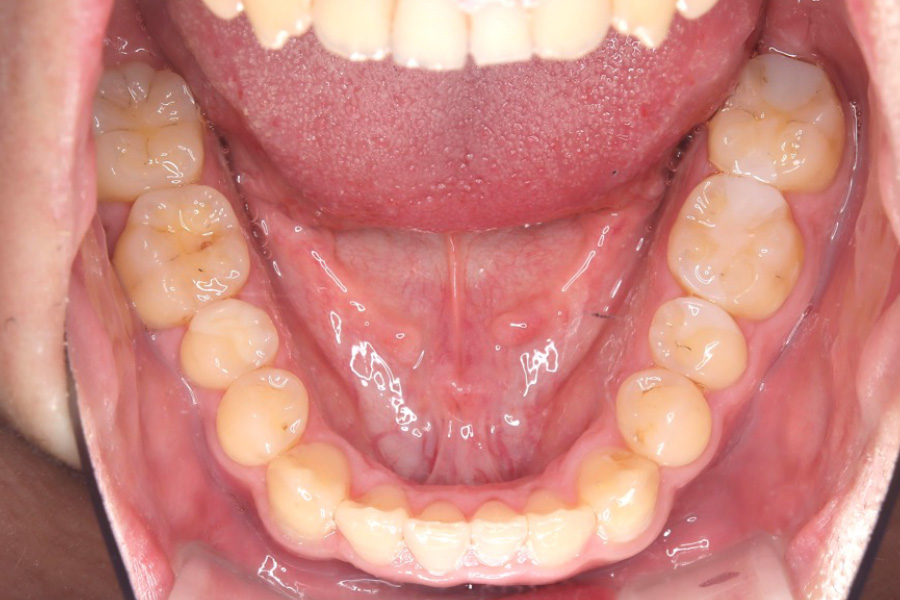

治療前

主訴 歯のガタつき

治療内容 インビザライン矯正

非抜歯